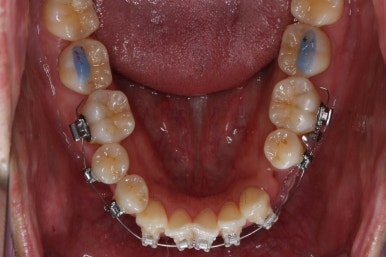

부산비수술교정 키다리아저씨치과에 처음 내원하셨을 당시의 입 안의 모습입니다.

아래 앞니에 결손치아가 하나 있네요. 송곳니-송곳니 사이에 앞니가 4개가 있어야 정상이지만 이 분은 3개에요. 의외로 아래앞니 하나 혹은 두개가 없는 경우가 굉장히 많답니다.

갯수가 맞지 않다보니 치열의 중앙도 맞지 않고 비대칭이 됩니다.

그리고 주걱턱이기 때문에 당연히 아랫니들도 앞으로 나올 수 밖에 없어 윗니보다 앞에 나와있어요.

이를 반대교합이라고 합니다.

이 분의 경우에도 전반적으로 잇몸이 약해져있을 수 밖에 없어요. 보시면 아시겠지만 잇몸 퇴축이 심해서 치아들이 길쭉길쭉해 보이죠.